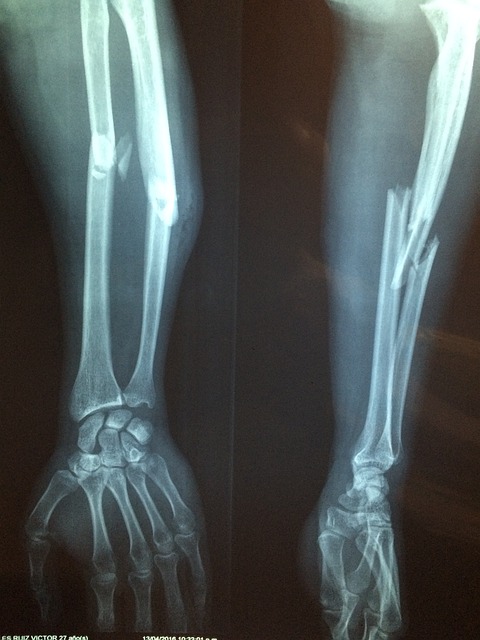

- 골다공증 예방: 연구에 따르면, 우슬은 뼈의 밀도를 증가시키고 골 손실을 방지하는 데 도움을 줄 수 있습니다. 이는 골다공증이나 다른 뼈 관련 질환을 예방하거나 관리하는 데 유익할 수 있습니다.